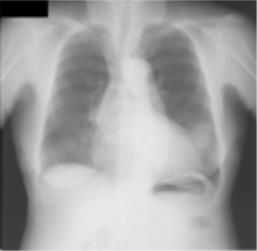

Thoracic disease detection from chest radiographs using deep learning methods has been an active area of research in the last decade. Most previous methods attempt to focus on the diseased organs of the image by identifying spatial regions responsible for significant contributions to the model's prediction. In contrast, expert radiologists first locate the prominent anatomical structures before determining if those regions are anomalous. Therefore, integrating anatomical knowledge within deep learning models could bring substantial improvement in automatic disease classification. This work proposes an anatomy-aware attention-based architecture named Anatomy X-Net, that prioritizes the spatial features guided by the pre-identified anatomy regions. We leverage a semi-supervised learning method using the JSRT dataset containing organ-level annotation to obtain the anatomical segmentation masks (for lungs and heart) for the NIH and CheXpert datasets. The proposed Anatomy X-Net uses the pre-trained DenseNet-121 as the backbone network with two corresponding structured modules, the Anatomy Aware Attention (AAA) and Probabilistic Weighted Average Pooling (PWAP), in a cohesive framework for anatomical attention learning. Our proposed method sets new state-of-the-art performance on the official NIH test set with an AUC score of 0.8439, proving the efficacy of utilizing the anatomy segmentation knowledge to improve the thoracic disease classification. Furthermore, the Anatomy X-Net yields an averaged AUC of 0.9020 on the Stanford CheXpert dataset, improving on existing methods that demonstrate the generalizability of the proposed framework.